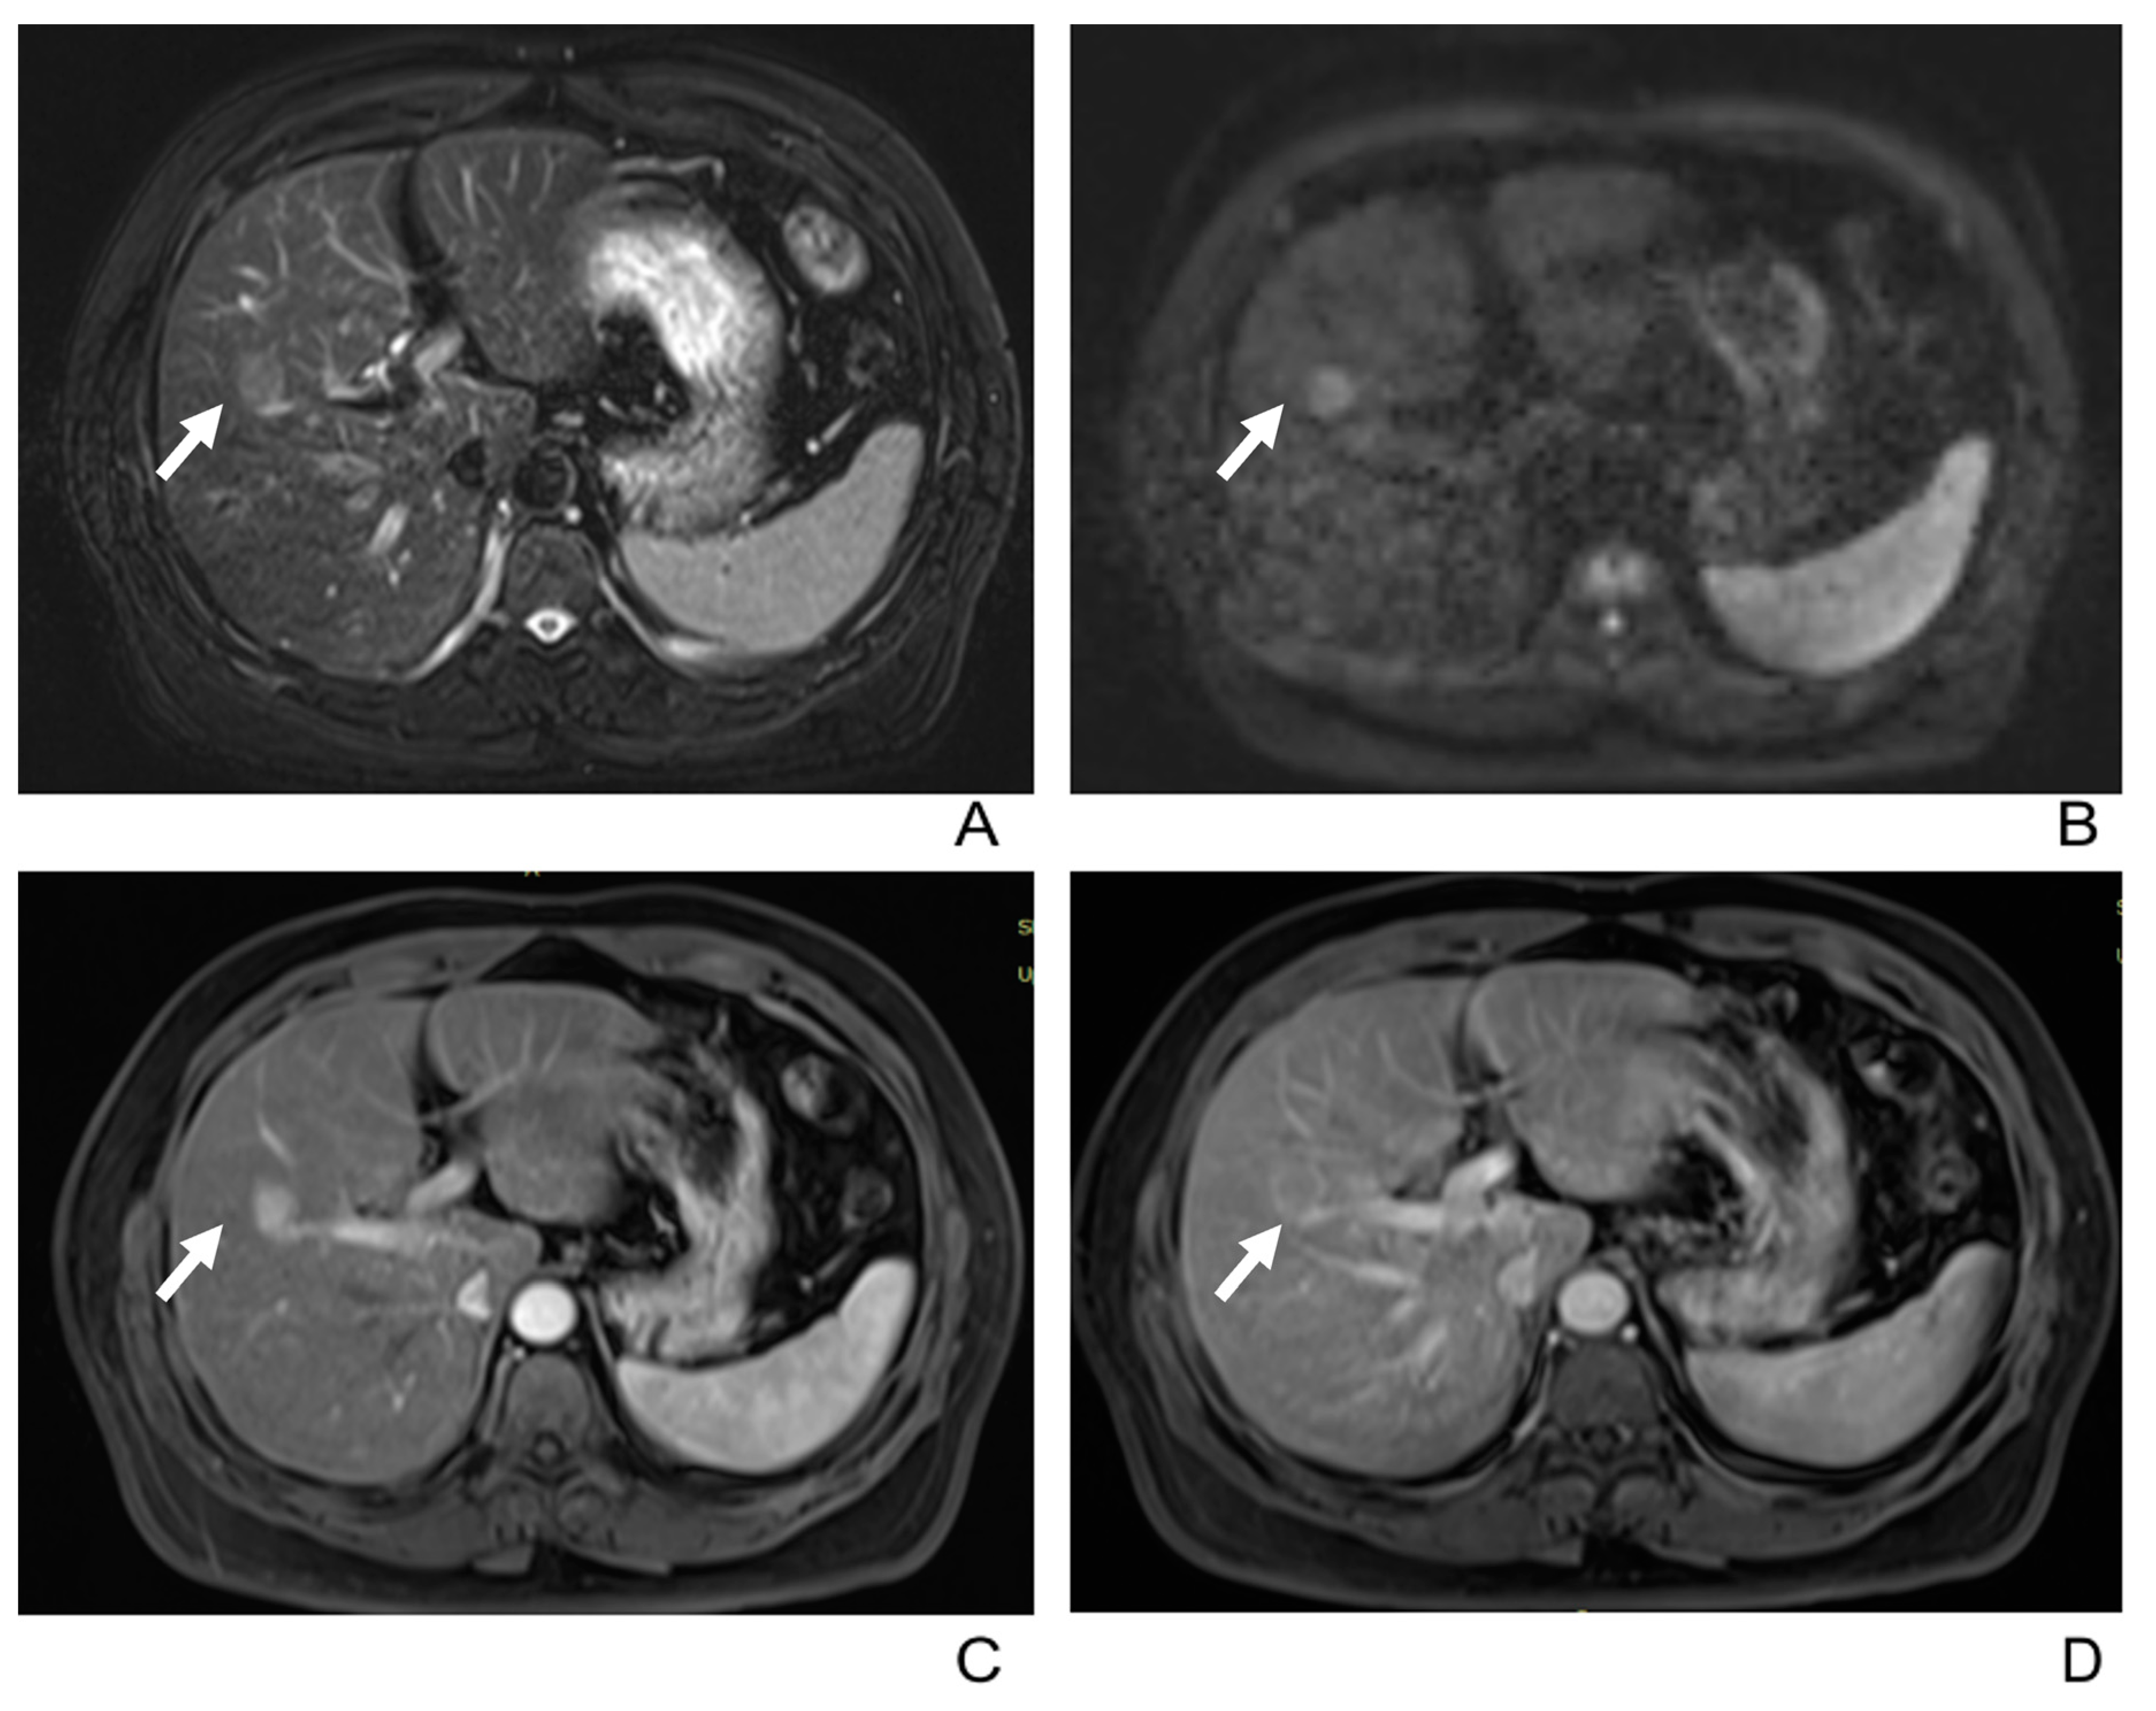

3.2. Imaging Manifestations

| Dynamic enhancement patterns | |

| Type A a | 21(55%) |

| Type B b | 10(26%) |

| Type C c | 7(18%) |

| Capsular enhancement | 22/38(58%) |

| Type A/Type B/Type C | 13/9/0/(62%/90%/0) |

- Type B: Nonrim arterial phase hyperenhancement with wash-out in PVP or DP, which resembles the “rapid wash-in and wash-out” seen in typical HCC.

- Type C: Nonrim arterial phase hyperenhancement with either consistent enhancement or isointensity in PVP or DP, or “rapid wash-in without wash-out”